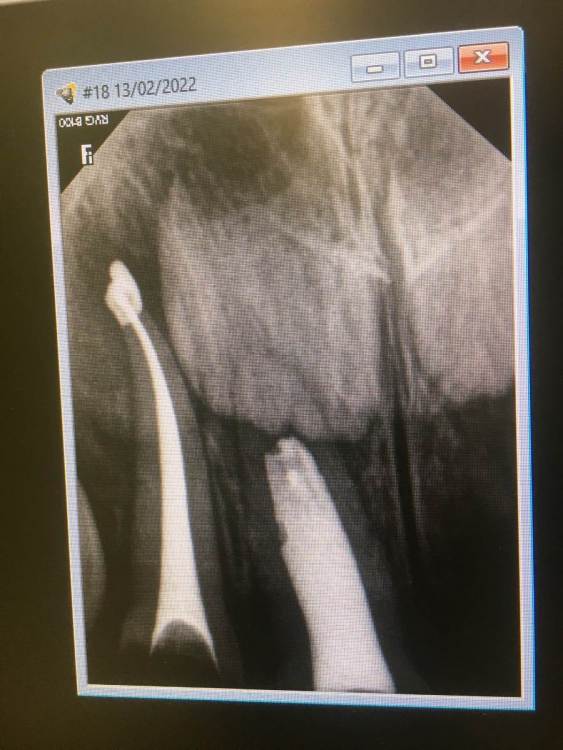

Здравствуйте, моей дочери 2 года. 12 дней назад ей пролечили под наркозом 3 верхних резца, пульпиты. На 2 зуба установили коронки, один реставрировали пломбировочным материалом. Сейчас прошло уже 12 дней, рядом с пролеченными зубками десна очень воспалены, красные и отечные. По рекомендации нашего врача мажем метрогил Дента, но улучшений нет. Подскажите, пожалуйста, в чем может быть причина? Неправильно установлены коронки? Есть Надежда, что воспаление пройдёт или необходимо будет ещё вмешательство?

Дело в том, что малышка не открывает рот врачам, любые манипуляции будут возможны только под повторным наркозом, чего очень не хотелось бы. Спасибо заранее за ответ.

51149846-34F3-49C2-BEB8-B065B6CC76A3.png09EDA12B-CD16-4E0D-B897-5C3D94E5A672.png